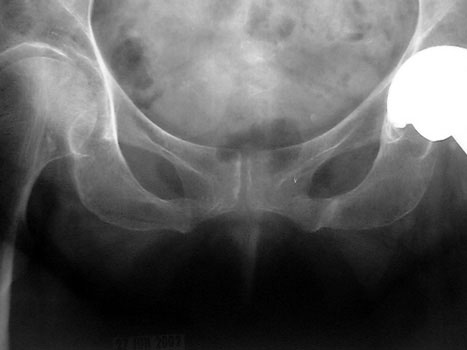

STRESS OR INSUFFICIENCY

Left pubic bone

Left inferior pubic ramus